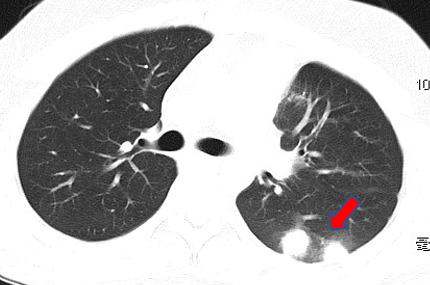

家住江苏的王小姐是个上班族,但平淡的生活却被一阵阵剧烈的咳嗽打断了。干咳到胸痛的王小姐感觉一分钟也忍不了了,半夜去急诊拍了胸部CT,医生看到双肺多发结节影,说不能除外肺癌。王小姐吓得心都提到了嗓子眼,赶紧到感染病科门诊看病。

医生看了王小姐病史,发现除了肺结节之外,她的血常规嗜酸性粒细胞更是高到飞起,详细一问,原来王小姐一直喜欢吃醉蟹,鲜嫩的口感让她欲罢不能。医生说,没有煮熟的蟹里很可能有寄生虫,换句话说,你在吃生螃蟹的时候,蟹里的虫也会吃你。

在医生建议下,王小姐抽血检查了寄生虫抗体,发现肺吸虫抗体阳性,于是明确诊断:肺吸虫感染。口服药驱虫治疗后,王小姐血常规逐渐恢复正常,胸部CT的结节也吸收了。至此,王小姐长吁一口气,马上在家族群里@所有人:以后都别吃这种没烧熟的东西了。